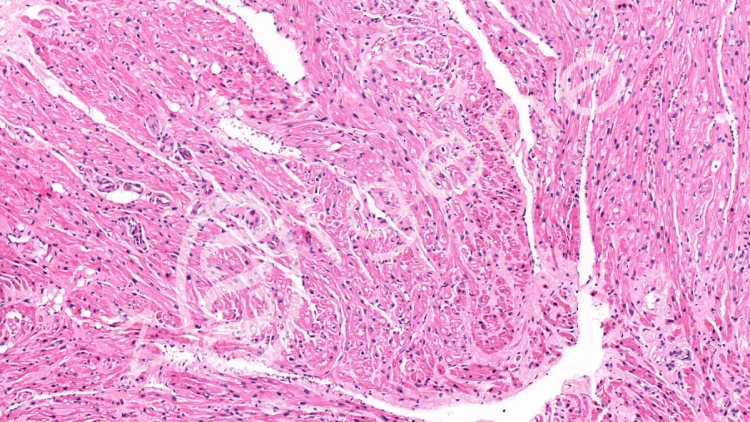

載基白光拍照可接收:石蠟切片、細胞爬片、冰凍切片等(切片盒保存運輸)。

結(jié)果交付:3個視野,2個倍數(shù),6張,常規(guī)同視野下200×3、400×3。默認圖片不加標尺,需要請在交接單上注明。也可后期在圖片的基礎上加;如無拍照要求,即按常見的部位拍,例如:肝中央靜脈、腦皮層海馬、腎小球等,特殊染色以及免疫組化陽性部位。特殊要求請?zhí)崆罢f明。